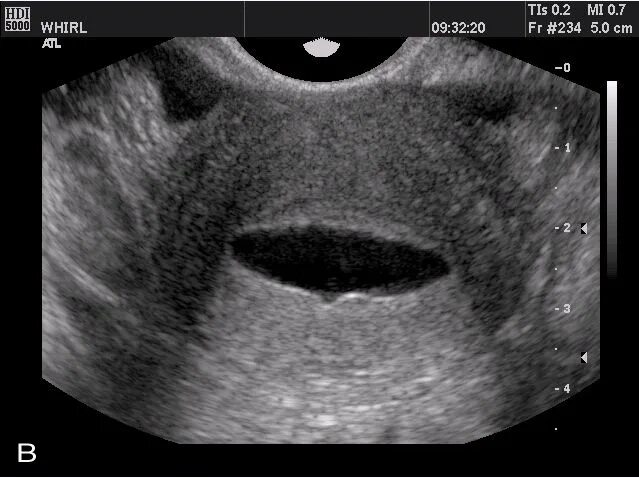

Серозометры в матке что это такое